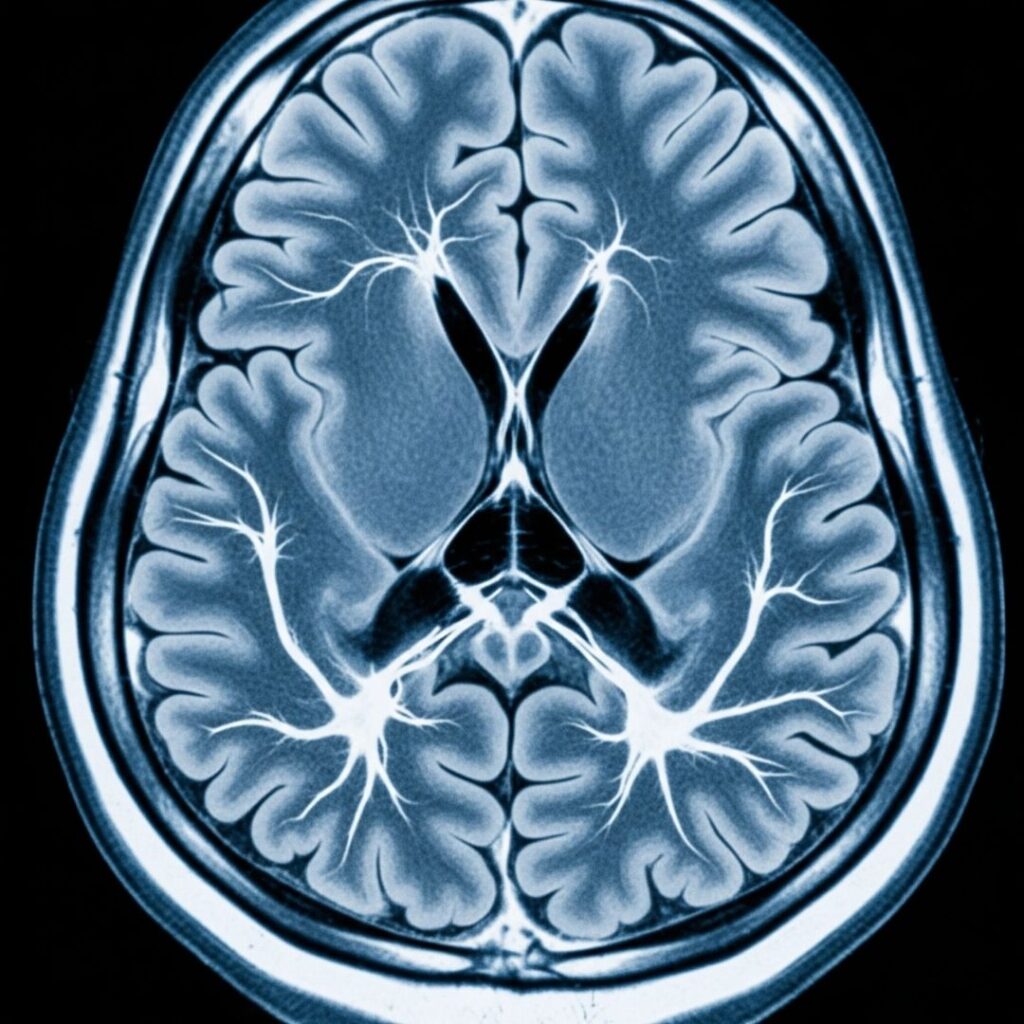

The Role of Education in Managing Neurological Conditions September 23, 2025 Understanding a neurological diagnosis is the first step toward effective Read More →